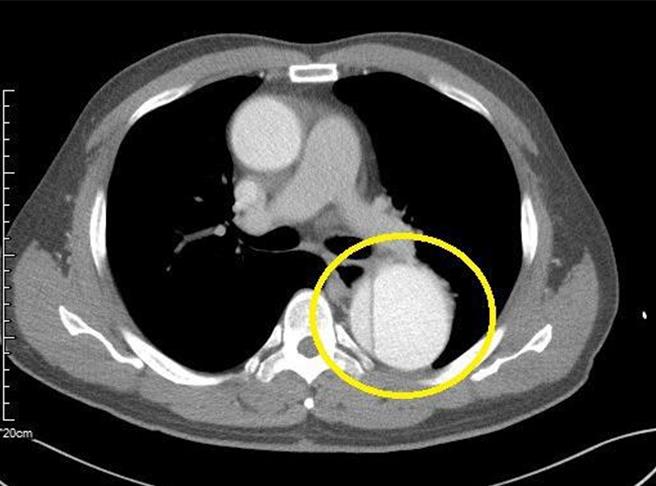

王男经门诊初步心电图、胸部X光检查后并无明显异常,经过与医师讨论后,安排至保康门诊接受多切面心臟电脑断层扫描,此检查可得知两项重要心臟疾病的指标,包括冠状动脉钙化程度、血管狭窄情形;不料,检查后出现惊人结果,王男罹患「胸腹主动脉剥离」,是一种相对严重心血管疾病,知名歌手潘安邦和艺人黄鸿升(小鬼)都是因该急症猝逝。

「胸腹主动脉剥离」如果未及时发现、治疗,会导致严重甚至致命併发症,包括心肌梗塞、脑中风、肺栓塞、急性肾功能衰竭等;王男因只有轻微胸闷,仍可进行日常活动,主因为主动脉出问题的部分在胸部腹部段(俗称:降主动脉),而非「升主动脉」,王男由心臟外科医师接手安排开心手术,目前已回家休养。

丰原医院放射科医师黄竣圣指出,MDCT电脑断层检查的最大优点是非侵入性,可以清楚显示冠状动脉、主动脉等血管的解剖结构,并找出血管硬化狭窄、动脉剥离、动脉瘤形成等异常,因此被广泛应用于心血管疾病的筛检及诊断。